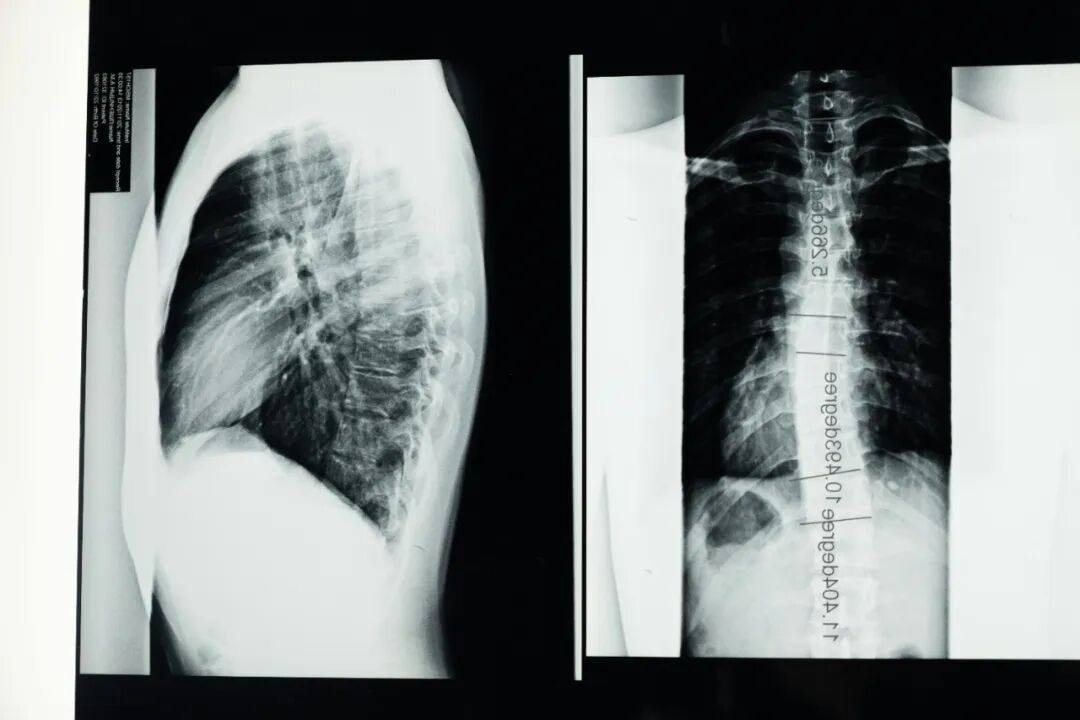

脊柱侧弯

不建议做的三项运动